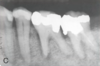

What is this radiographic finding?

Periapical Cysts

►Would need to test both teeth for vitality.

What is this radiographic finding?

Periapical Cyst